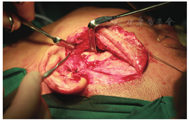

广州医科大学附属口腔医院颞下颌关节病科通过3万余例TMD患者临床诊疗经验,提出了"序列化、微创化、数字化、舒适化、人文化"的特色诊疗模式[4]。第一阶段为保守治疗,具体治疗方案是关节腔注射治疗(关节腔内注射透明质酸钠,图2)联合关节咬合板治疗,再辅以理疗、药物治疗和手法复位,有效率达85%左右,是TMD患者选择最多也是最佳的"一线"治疗方法。少数患者对于保守治疗效果不佳,如疼痛、绞锁、开口限制未得到改善,笔者团队会建议患者进行第二阶段治疗,即关节镜微创治疗(图3),这可进一步提供辅助诊断以及治疗作用。关节镜治疗可对病变关节进行灌洗、黏连松解、清除黏连物、骨组织修整以及关节盘复位,此法对于保守治疗无效的TMD患者有肯定的疗效。第三阶段为开放性手术(图4),因颞下颌关节盘前移位导致长时间疼痛和功能障碍,因外伤、关节盘前移位及骨关节病导致的关节盘穿孔,或颞下颌关节镜微创治疗疗效不佳并愿意接受此法的患者,施行颞下颌关节盘复位锚固术或关节盘穿孔修补术。本文重点阐述"序列梯度"治疗中"保守治疗"的一种临床治疗方法——"颞下颌关节咬合板"治疗。